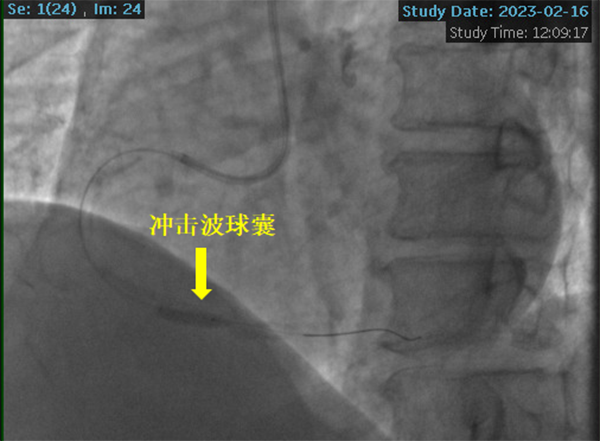

冠脈鈣化病變被稱為“最硬的骨頭”或“最堅硬的堡壘”, 可導致介入器械難以通過或不能通過病變,即刻成功率低,并發(fā)癥發(fā)生率高等嚴重后果。針對患者病情及冠脈病變的復雜性,潘德鋒主任決定采用被譽為“拆彈專家”的沖擊波球囊技術(shù)治療冠脈嚴重鈣化病變。

2023年2月16日,在副院長楊煜的統(tǒng)籌指導下,心內(nèi)科冠脈專業(yè)專家組夏勇主任、徐通達主任、錢文浩主任、徐晤主任、陸遠主任等針對病例進行了充分的討論及術(shù)前準備,由潘德鋒主任進行手術(shù)操作。術(shù)中首先利用血管內(nèi)超聲明確患者冠狀動脈的鈣化情況及血管直徑,在血管內(nèi)超聲的指導下,選擇了4.0mm×12mm的沖擊波球囊,順利送入沖擊波球囊至鈣化病變部位,釋放脈沖,每次釋放10個脈沖,最終通過釋放80個脈沖,將鈣化斑塊進行了充分預處理,成功為患者植入了一枚冠脈支架,術(shù)后血管內(nèi)超聲顯示支架貼壁良好,患者癥狀明顯緩解,2月18日康復出院。